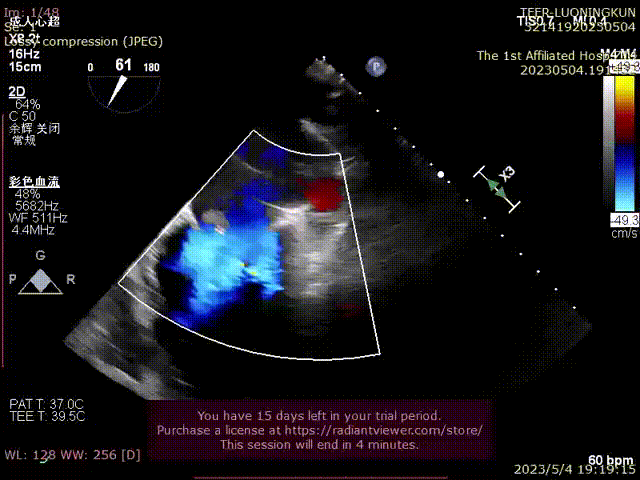

术前二尖瓣大量反流,脱垂宽度超过20mm,主要为P2区及部分P3区

手术经股静脉-房间隔入路,采用全身麻醉插管,在TEE和DSA引导下完成房间隔穿刺。置入JensClip瓣膜夹系统后,在左房调整瓣膜夹的位置和轴向,后进入左室,在TEE引导下捕捉二尖瓣前后瓣叶,并关闭瓣膜夹。经TEE反复确认手术效果后最终锁定并释放瓣膜夹。由于该病例二尖瓣后叶P2区及部分P3区脱垂,脱垂范围宽度达20mm,术中植入了两枚长宽(LW)的瓣膜夹。术后即刻超声显示瓣膜夹位置稳定,功能良好,二尖瓣反流由术前4+减少至微量,肺静脉逆流和左房压都显著好转,手术圆满成功。术后患者状态良好,目前已安排出院。

第一枚瓣膜夹植入于P2P3位置,植入后内侧反流消失